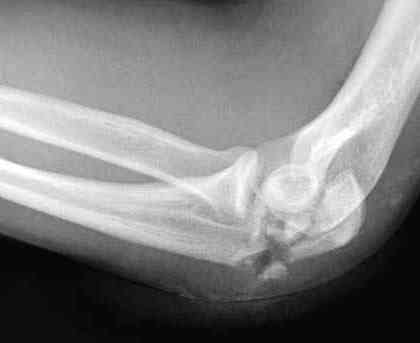

Уважаемый Владимир! Судя по представленному снимку перелом многооскольчатый, но снимок сделан в транспортной иммобилизации видимо при поступлении. Необходимы снимки в стандартных проекциях, чтобы можно было, что-нибудь посоветовать. При данном переломе главное попытаться восстоновить суставную поверхность локтевой кости, поэтому я бы посоветовал идти стандартным путем, разрез Z- образный, крупные отломки фиксировать спицами и если получится стягивающей проволочной петлей, под которую уложить мелкие отломки. Своего мнения не навязываю.

Good day dears colleagues! You presentated only one x-ray proection - lateral- of elbow.Accorden this I thing that this isn't avulsion fracture of olecranon,as usually can to see.This is Monteggia like fracture with subluxation of radial head.If

you can show AP x-ray or more more better CT elbow

I will more sure.Any way more imported of all normal long of ulna.So my recomendation ORIF proximal ulna by LCP - allow normal long by bridging, without attention to continues cortex but attention to articular surfase. On operation examen of radial head,becouse my sence isn't without damage.Operation by standart approach.

Снимок, действительно, "не очень". Но глядя на него почему-то возникает очень сильное ощущение, что там и венечный отросток сломан тоже. Что ситуацию здорово усложняет. Причём перелом венечного "III типа" - очень крупный фрагмент, отломанный под самое его основание. А это (без фиксации) уже грозит задней, а возможно - и фронтальной (вальгусной/варусной) нестабильностью.

Это не перелом локтевого отростка! Безусловно сломан венечный отросток и, может оказаться, что и головка луча. Сложный перелом! Доступ задний, фиксация пластиной (LCP) и стягивающими винтами. Только не по Веберу! Положение больного на животе. ЭОП.

При самом большом к Вам уважении, Сергей Анатольевич, не соглашусь. У меня, после того, как добавили "прямой" снимок, сомнений не осталось. Венечный сломан наверняка. Но чтобы судить, насколько это критично для стабильности, нужно иметь строго боковую проекцию. И при этом помнить, что на него крепятся медиальные связки.

Прикрепляю снимок, где обведен фрагмент, несущий на себе венечный отросток (весь он смещён с этим фрагментом или частично - без качественной боковой проекции судить сложно), и отдельно на снимке обведено "ложе", от которого он сместился.